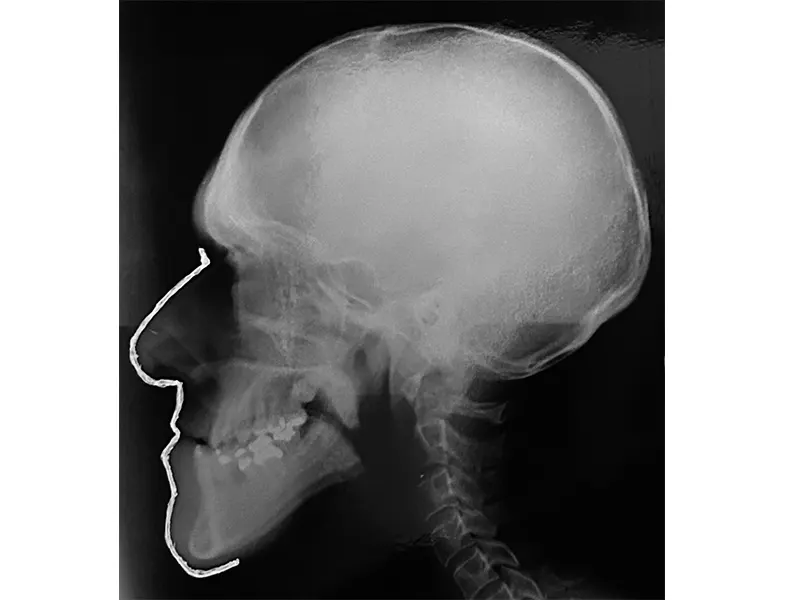

Φωτογραφίες Πριν και Μετά την Επέμβαση

Στην πρώτη υποενότητα, παρουσιάζονται συγκριτικές φωτογραφίες πριν και μετά την επέμβαση. Οι εικόνες αυτές αναδεικνύουν την εξέλιξη της κατάστασης του ασθενούς και την αποτελεσματικότητα των εφαρμοσμένων θεραπευτικών μεθόδων.